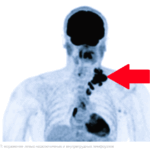

• КТ, МРТ, ПЭТ-КТ: эти методы позволяют увидеть глубоко расположенные лимфоузлы (в брюшной полости, в грудной клетке), которые нельзя прощупать руками. ПЭТ-КТ особенно эффективен для поиска метастазов, так как «подсвечивает» даже небольшие скопления активных раковых клеток.

Множество научных статей демонстрируют превосходство ПЭТ – КТ в определении стадии заболевания для многих видов рака.